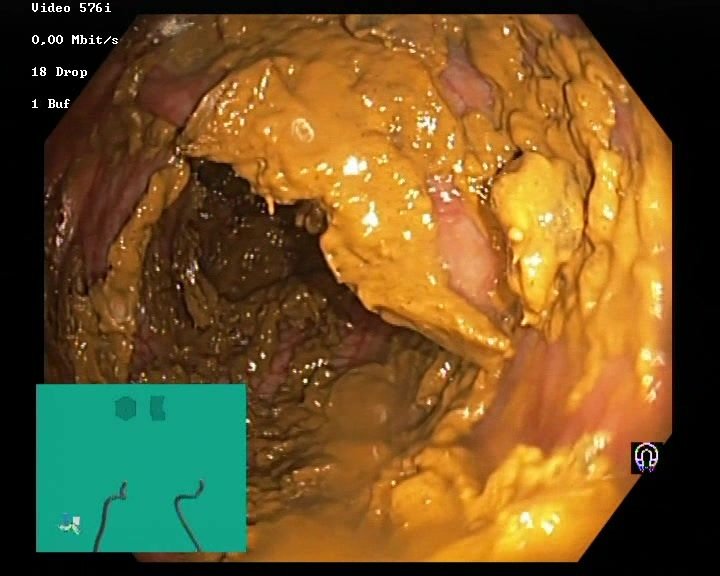

The Kvasir Dataset

Dyed lifted polyps

Dyed resection margins

Polyps

Ulcerative colitis

Normal cecum

Esophagitis

Normal z-line

Normal pylorus